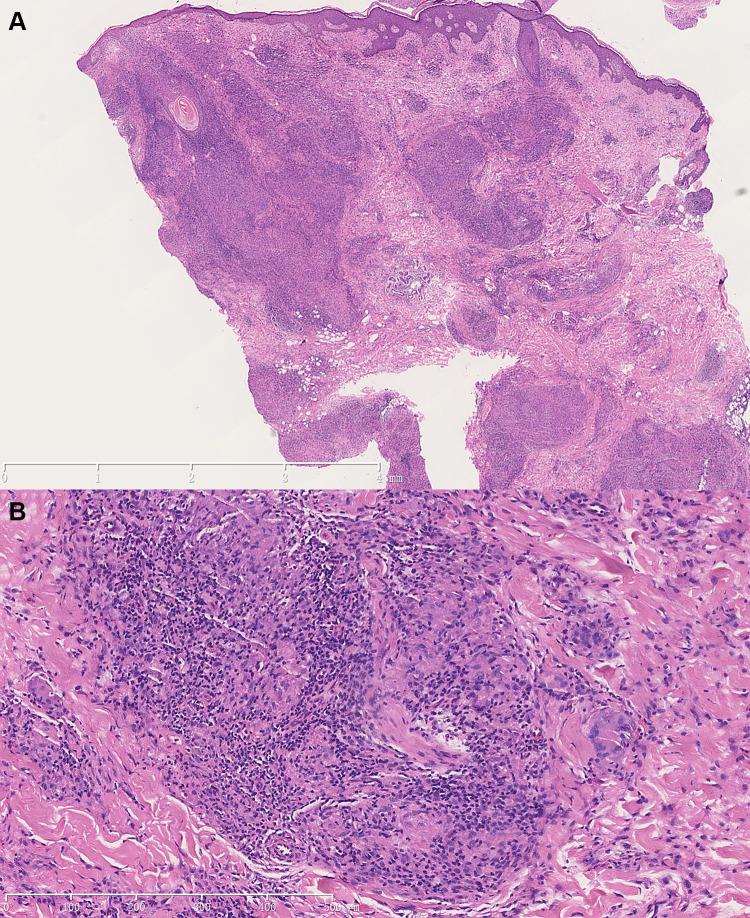

Lupus vulgaris is a paucibacillary form of cutaneous tuberculosis (CTB) which is accounting for 1-2% of all tuberculosis cases. Here, we report a rare huge lupus vulgaris misdiagnosed as sarcoidosis for 11 years. A 65-year-old man presented to dermatology outpatient with a large asymptomatic erythematous plaque and erosions on his neck. Sarcoidosis was initially diagnosed on the basis of negative interferon-gamma release tests and biopsies of lymph nodes and lesions. The patient was treated with long-term oral steroid and immunosuppressive agents, but the lesions expanded gradually. Lupus vulgaris was finally diagnosed by combining molecular detection and mycobacterial culture. The skin lesions were resolved after six months of standard antituberculosis therapy. We report this case to analyze the reasons for the misdiagnosis and review-related literature to further provide experience for the diagnosis and treatment of cutaneous tuberculosis with negative T-SPOT.TB.

寻常狼疮是一种少菌型皮肤结核(CTB),占所有结核病例的1-2%。在此,我们报告一例罕见的巨大寻常狼疮,被误诊为结节病达11年之久。一名65岁男性因颈部出现一个大的无症状红斑斑块及糜烂而就诊于皮肤科门诊。最初根据干扰素-γ释放试验阴性以及淋巴结和病变活检结果诊断为结节病。患者接受了长期口服类固醇和免疫抑制剂治疗,但病变逐渐扩大。最终通过分子检测和分枝杆菌培养相结合确诊为寻常狼疮。经过六个月的标准抗结核治疗后,皮肤病变得以消退。我们报告此病例以分析误诊原因并回顾相关文献,以便为T-SPOT.TB阴性的皮肤结核的诊断和治疗进一步提供经验。